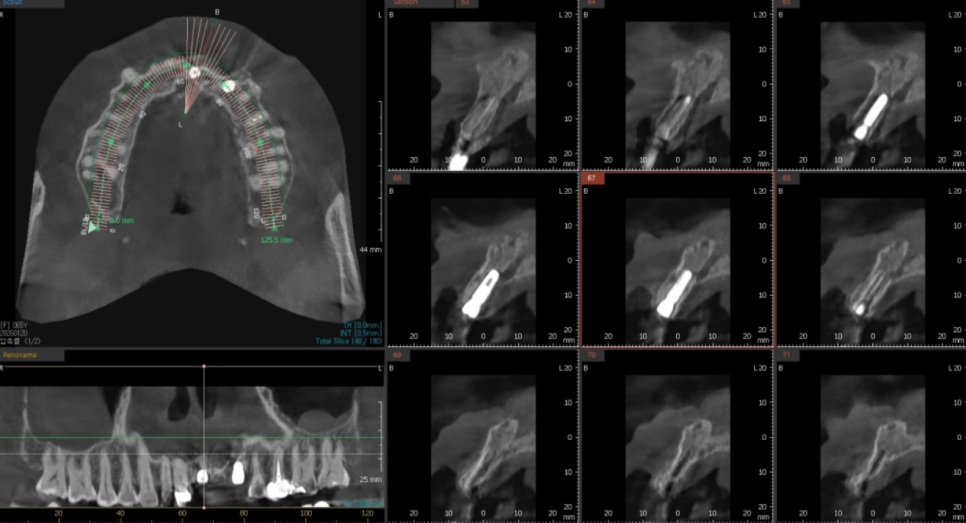

탐침 기구로 체크해 보니,

보철 안쪽으로 기구가 완전히 통과될 정도로

내부 공간이 벌어져 있었는데요~

방사선 사진을 살펴보니 역시나,

2차 충치로 인해 치아 뿌리와 보철물 사이가

완전히 끊어져있네요.. ㅜㅜ

더 자세히 확인하기 위해

기존 브릿지를 제거해 보니,